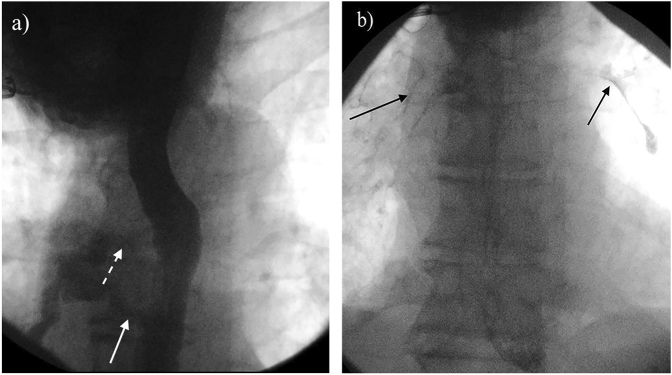

获得性良性气管食管瘘和支气管食管瘘(TEF)通常与肉芽肿性纵隔感染有关,其中75%是先天性的。白色念珠菌(Candida albicans)和放线菌(Actinomyces)是常见的病原体,但 TEF 的病因并不常见。这些病原体的正常定植和某些种类生长缓慢的特点很少导致感染、霉菌瘤和支气管胆石症,因此很可能延误诊断和治疗。很少有报道称白僵菌或放线菌是 TEF 或支气管胆石症的病原体。在此,我们报告了一例继发于白色念珠菌和放线菌共同感染的良性获得性 TEF 病例,该病例并发放线菌瘤的形成和支气管胆石症,我们还进行了全面的文献综述,以强调该病例的特殊性,并提供 TEF 的诊断和治疗算法。在出现三个月的有痰咳嗽、窒息感、盗汗和体重减轻后,支气管镜检查发现食管和右中叶后部之间有瘘管连接。病理检查发现了一个钙化的真菌球和一个继发于念珠菌和放线菌共同感染的支气管结石。这种念珠菌和放线菌合并感染的独特表现形式以及相关的诊断算法将为临床医生提供教育和有用的工具。

Acquired benign tracheoesophageal fistulas and bronchoesophageal fistulas (TEF) are typically associated with granulomatous mediastinal infections, 75% of which are iatrogenic. Candida albicans and Actinomyces are commonly occurring organisms, but are uncommon etiologies of TEF. Normal colonization and the slow growth characteristics of some species of these agents rarely result in infection, mycetoma, and broncholithiasis, and thus, delays in diagnosis and treatment are likely. Few reports describe C. albicans or Actinomyces spp. as the etiology of TEF or broncholithiasis. Herein, we report a case of benign acquired TEF secondary to coinfection of Candida and Actinomyces complicated by the formation of an actinomycetoma and broncholithiasis and a comprehensive literature review to highlight the unique nature of this presentation and offer a diagnostic algorithm for diagnosis and treatment of TEFs. Following a presentation of three months of productive cough, choking sensation, night sweats, and weight loss, a bronchoscopy revealed a fistulous connection between the esophagus and the posterior right middle lobe. Pathology identified a calcified fungus ball and a broncholith secondary to the co-infection of Candida and Actinomyces. This unique presentation of Candida and Actinomyces co-infection and the associated diagnostic algorithm are presented as education and a useful tool for clinicians.